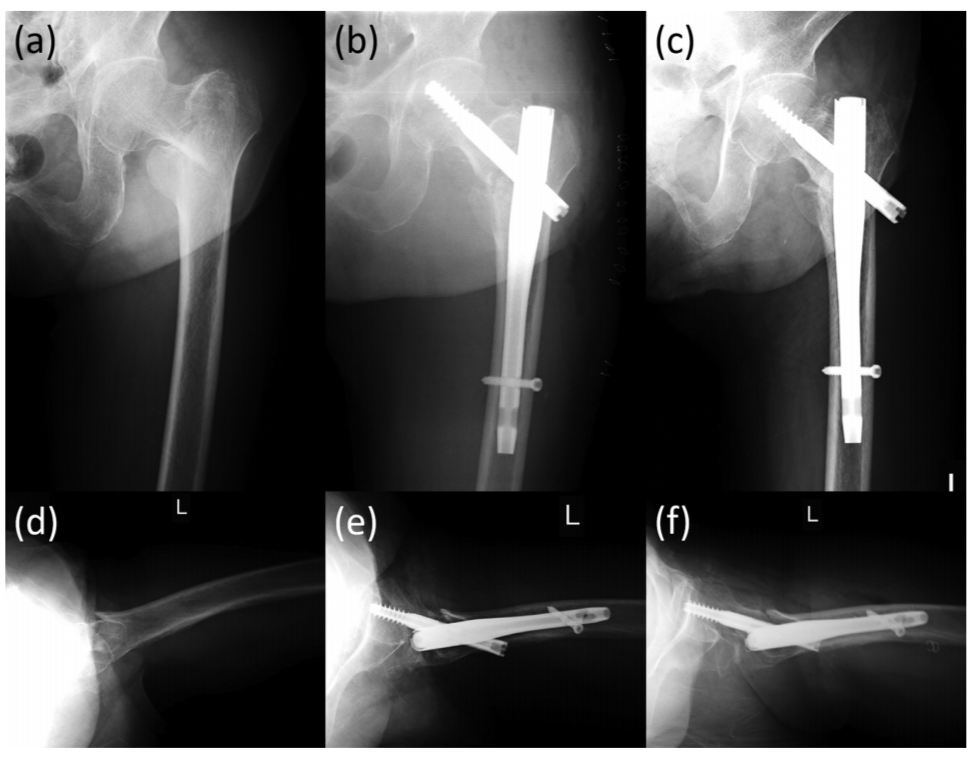

图3 一例92岁股骨粗隆间骨折患者,可见在正位片及侧位片上,骨折均良好显示。

图4 一例89岁股骨粗隆间骨折患者,可见在正位片骨折显示良好,在侧位片上后区由于金属内植物遮挡,骨折部位显示不清。